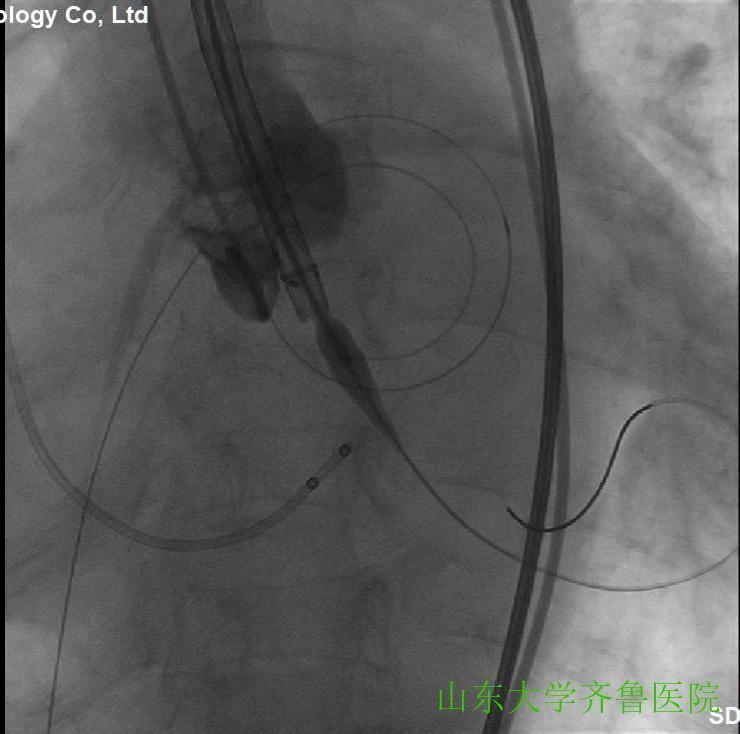

在手术室护士长翟永华及其护理团队、麻醉科吴剑波主任医师和杨绍忠主治医师的大力支持下,由心血管外科谷兴华主任医师、急诊心内科李传保主任医师、心内科安贵鹏副主任医师、心血管外科孙厚荣副主任医师及刘凯副主任医师、心脏超声室刘艳副主任医师和曹媛主治医师、放射科邵汉宏技师等在医院复合(Hybrid)手术室行一站式经导管主动脉瓣置换术(TAVR)+经皮二尖瓣球囊扩张成形术(PBMV)。手术先常规经颈静脉于右心室放置临时起搏导线并放置经食道TEE探头,行主动脉根部造影,明确主动脉瓣环平面、主动脉瓣钙化及返流情况(图1),导丝跨瓣入左心室并更换猪尾导管,测主动脉瓣跨瓣压差为76mmHg。选用24mm的擎源二尖瓣扩张球囊扩张2次,二尖瓣口面积由0.78?扩大至1.43?,并且二尖瓣无返流(图2)。选用20mmNuMed球囊,临时起搏心率180次/分,扩张狭窄的主动脉瓣(图3),应用26mmVenusA主动脉瓣介入瓣膜,准确定位、释放,造影、多体位透视及术中TTE显示介入主动脉瓣膜形态满意、无瓣周分流(图4-6)。术后即刻主动脉瓣最大跨瓣压差将至2mmHg。手术顺利,手术用时1小时40分钟,术后患者安返心脏外科监护病房。

图2应用24mm的球囊行二尖瓣球囊扩张